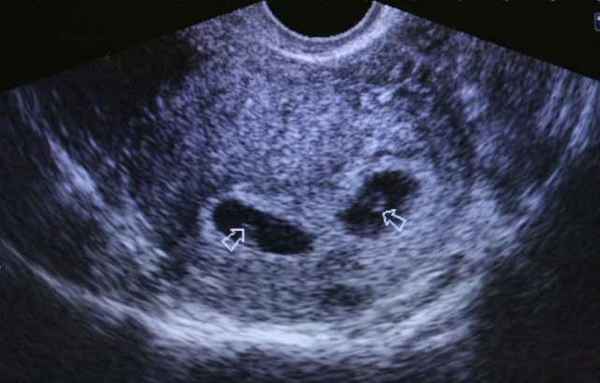

Экстракорпоральное оплодотворение не является гарантией успешной беременности. Оно лишь дает шанс паре стать родителями. В одном случае хватает единственной попытки, в другом требуется несколько.

Кроме того, вероятность удачного ЭКО – не более 60%. Четверть попыток заканчивается многоплодной беременностью – двойняшки или тройняшки. Все зависит от количества пересаженных зародышей. Но у части пациенток есть вероятность замершей беременности, внематочной или самопроизвольного прерывания развития плода.

Двойня на УЗИ

Поэтому проведение УЗИ на раннем сроке крайне важно. Оно точно устанавливает наступление беременности и то, насколько жизнеспособен плод. На УЗИ после ЭКО специалист выясняет:

- Произошло ли имплантирование зародыша в эндометрий матки.

- Местонахождение оплодотворенного плодного яйца – в матке, трубах или яичниках.

- Сколько эмбрионов, все ли они живые.

- Состояние яичников, чтобы скорректировать заместительную терапию.

УЗИ на таком раннем сроке беременности позволяет выяснить наличие самых опасных патологий развития плода.